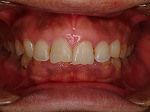

歯をより白く綺麗にしたいと思う方々は多いと思います。審美歯科とは、白い歯が見える口元だけではなく、機能的で歯周組織と顔貌に調和した自然美を追求する治療です。治療は短期間(歯冠修復・ホワイトニングなど)で終わるものから長期に渡る全顎的な治療(歯周病治療・矯正治療・インプラント治療など伴うケース)を行う症例もあります。当院での歯冠修復は

- ジルコニアクラウン修復

- メタルボンドクラウン修復

- グラスセラミッククラウン修復

- ハイブリットインレー、アンレー修復

- コンポジットレジン充填

等の歯冠修復を行っています。